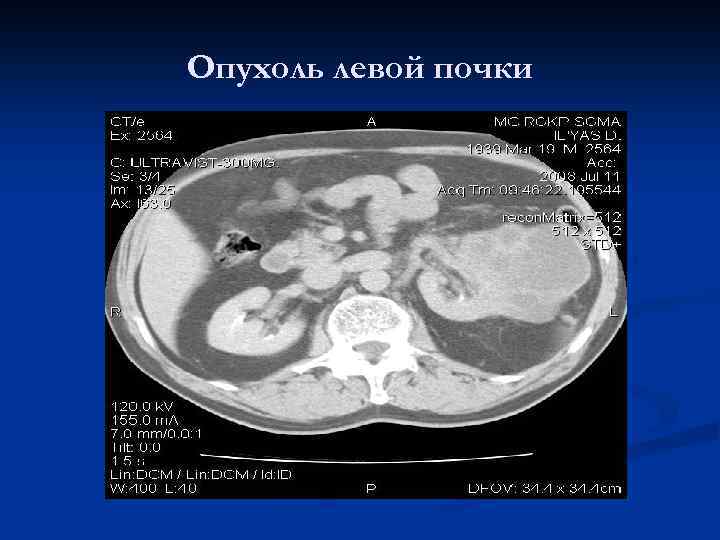

Опухоль левой почки